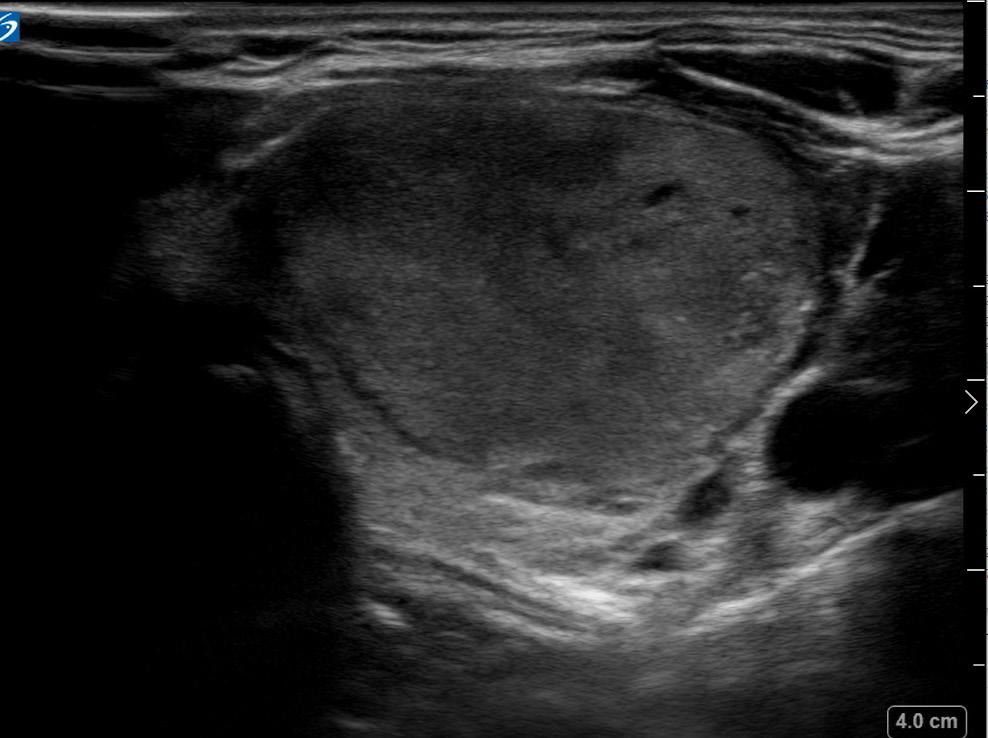

During her physical exam, I noticed the patient had a protuberant thyroid on the left side of her neck, causing cosmetic deformity and easily visible in any neck position. Ultrasound imaging confirmed the patient had multiple

thyroid nodules. She had no overt manifestations of thyrotoxicosis such as tremor, tachycardia, flushing or diaphoresis. She had no evidence of thyroid eye disease or exophthalmos. She was otherwise well appearing with a normal neurological examination.

Thyroid Ultrasound

The right lobe was heterogeneous with parenchymal hypervascularity, measuring 4.9 x 1.5 x 1.1 cm. There were three nodules present, all of them less than a centimeter in size. None of the nodules had highly suspicious features. The isthmus also had no significant nodules and was not thickened.

The left lobe was heterogeneous and measured 5.5 x 2.4 x 2.4 cm, with two notable nodules in her left thyroid lobe. There was a smaller mostly cystic nodule, which measured 2.2 x 2.1 x 2.2 cm. She also had a larger heterogeneous,

hypervascular solid nodule that contained internal microcalcification located in the left middle inferior lobe. This nodule measured 3.0 x 3.1 x 2.3 cm (calculated tumor volume = 11.3 mL).

When comparing the imaging to the nuclear medicine iodine scan, the dominant left solid hypervascular nodule appeared to correspond to the area of increased uptake on the thyroid scan, and clinically this was deemed most certainly the hot or toxic nodule.